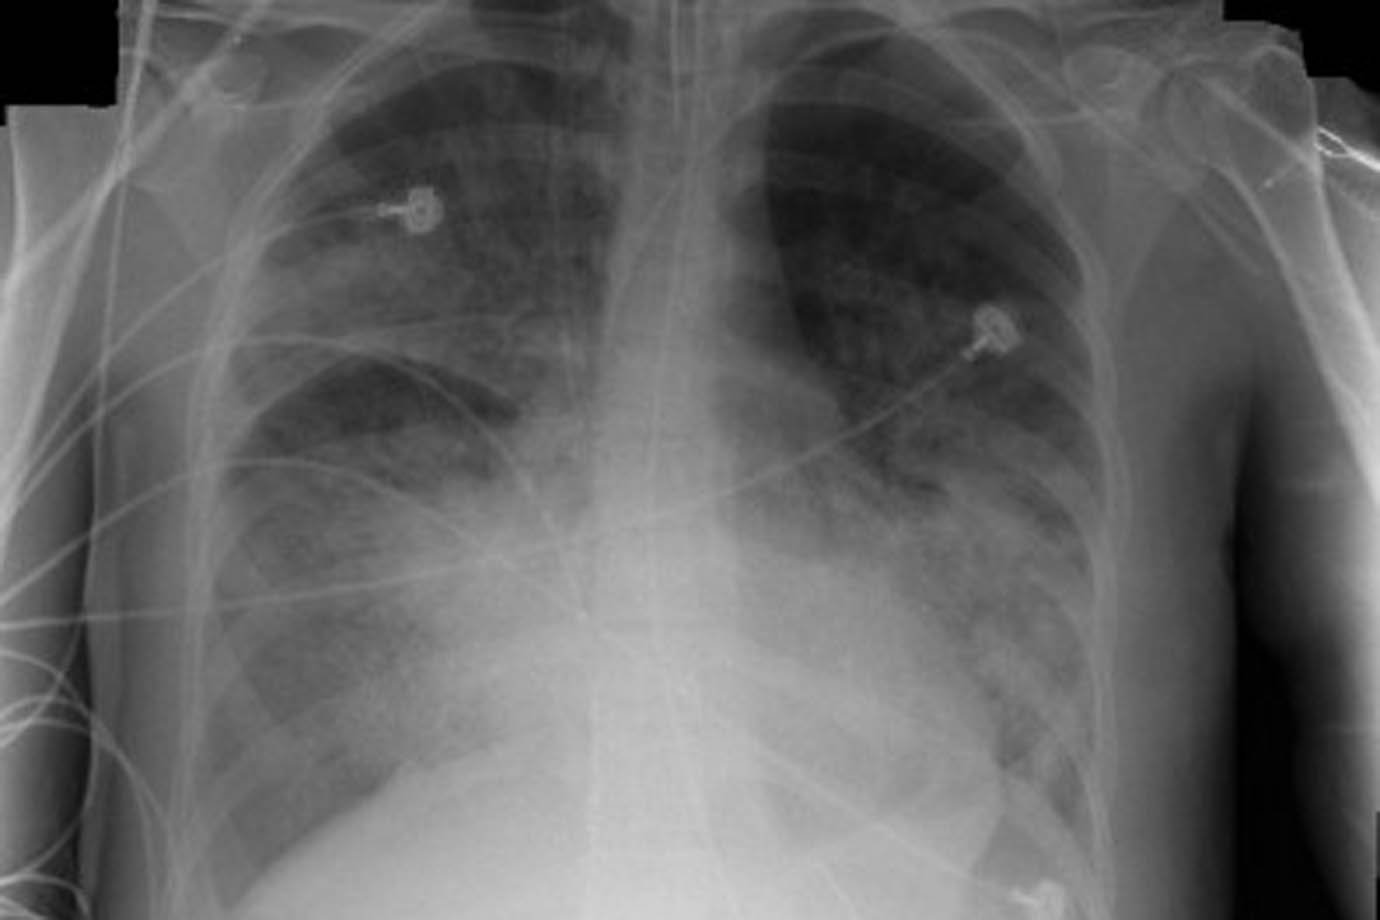

Droga experimental capaz de estimular tipo específico de receptor nicotínico em células imunes reverteu em camundongos quadro crônico e agudo de inflamação do pulmão (SRDA/Wikimedia Commons)